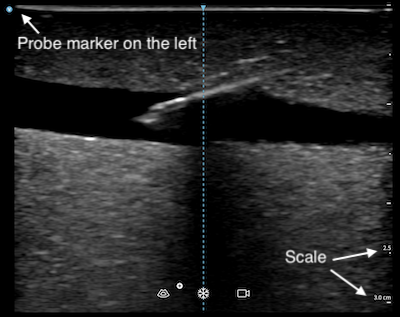

- Conventionally, while using a linear probe with the vascular preset, the image marker would appear on the left side of the screen. You should make sure the physical probe marker, which may be a notch or an embossed dot on the side of the device, is also on the left before scanning. You may confuse yourself with a mirror image if they are not aligned.

- The depth is shown in centimetre (or other units as specified) on the scale located on the right side of the screen. You can also use that as a reference to estimate dimensions of the structures you scanned.